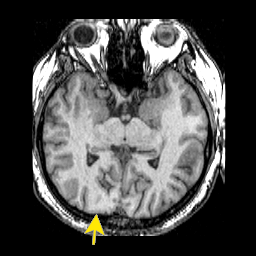

coupes transversales cortex sensoriels primaires |

vue transaxiale

Occipital et

Vision |

Temporal et Audition